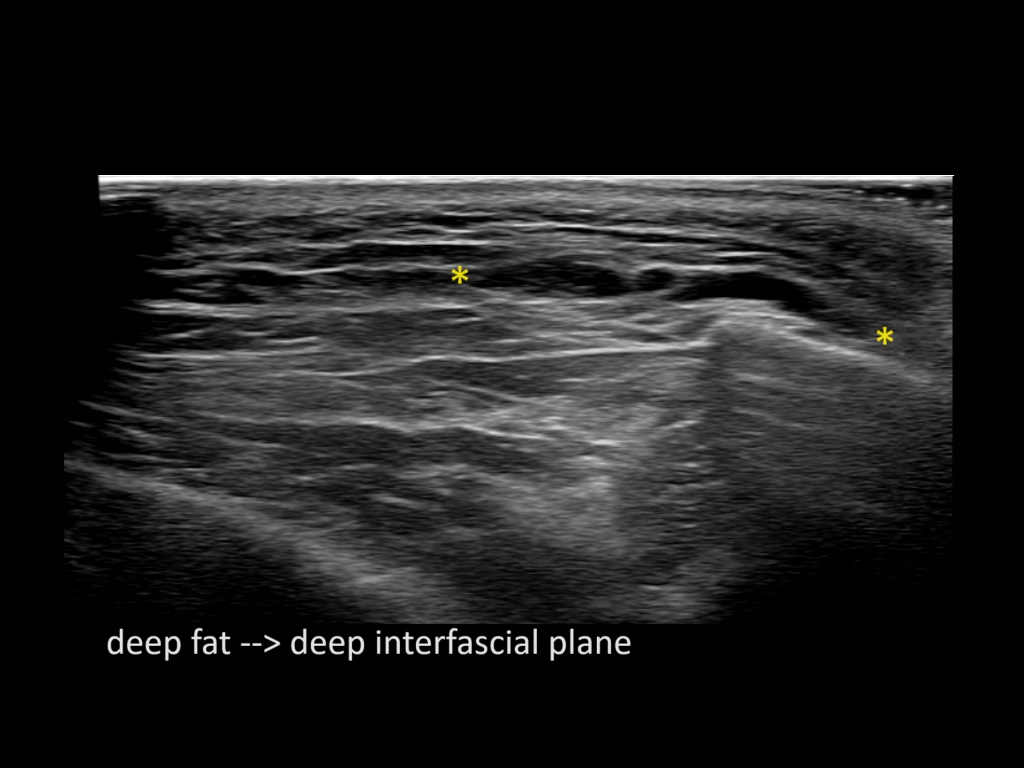

Filler behavior - Temple zygoma US

Study the first image to recognize the different layers. If you are sure about the layers, swipe to the second image to view the answer (if applicable).